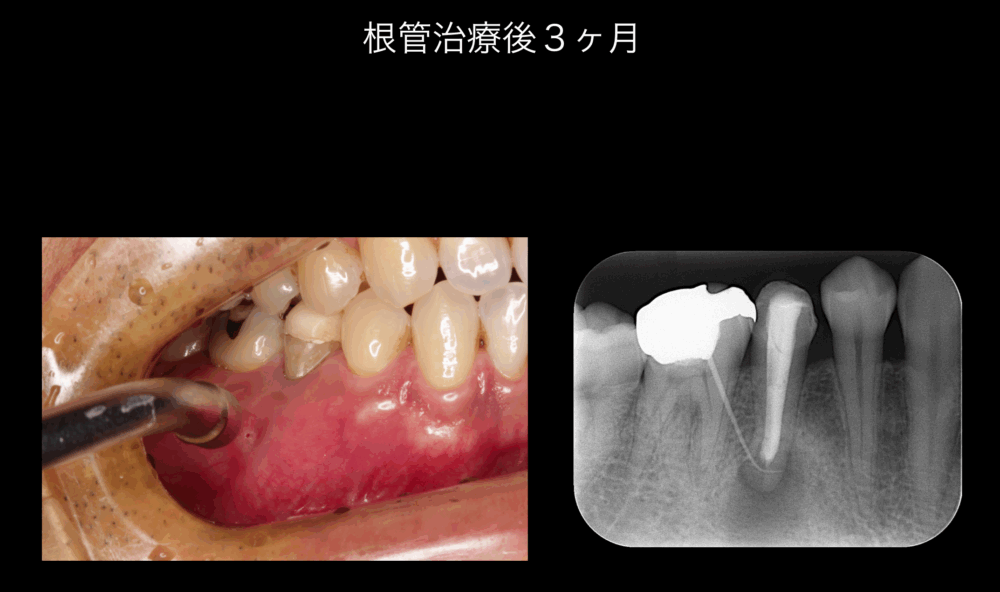

根管治療後3ヶ月で経過観察を行いました。

サイナストラクトにエアーを吹きかけると、瘻孔が見えます。ポイント造影では、右下5根尖部透過像に到達します。

コンセプトを遵守した根管治療を行ってもサイナストラクトは治癒しませんでしたので、歯根端切除術を施行することになりました。